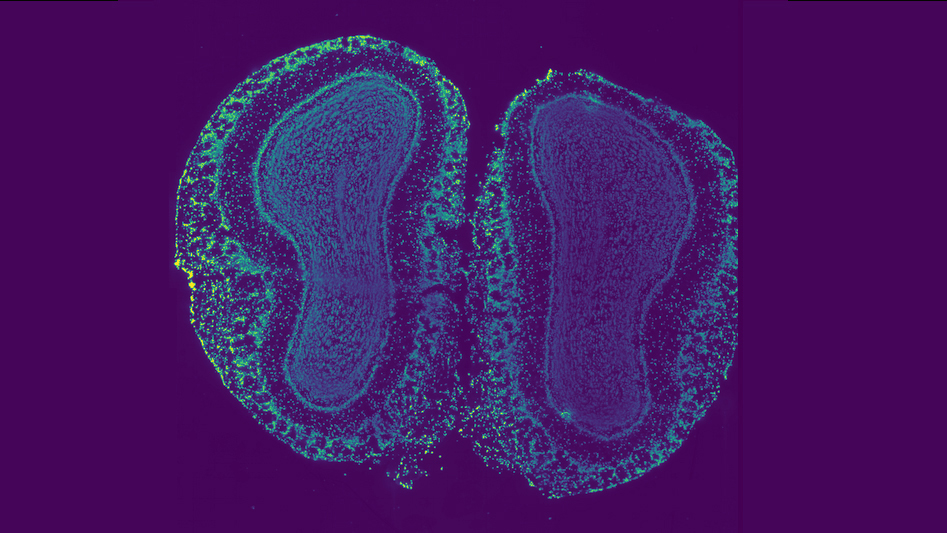

Using a new deep learning algorithm, researchers at Princeton have designed an approach to map the cellular organization of tissues by modeling spatial patterns in molecular data. 🧵

“Biological tissues are organized into intricate spatial structures that are important for their function,” said @benjraphael. “But it’s very hard to directly measure tissue organization from molecular data. This method reveals the hidden geometry.”

Using a new deep learning algorithm, researchers at @Princeton have designed an approach to map the cellular organization of tissues by modeling spatial patterns in molecular data. https://t.co/899N66Lmtr

New work in @Nature from @benjraphael, in collab with Josh Rabinowitz's lab. Raphael's lab developed an algorithm that maps cell tissue in 3D by tracking gene expression. The team @princetonchem used this to capture an organ's spatial metabolic organization. Learn more 👇

Congratulations Josh Rabinowitz Lab in collab with the Ben Raphael Lab of @PrincetonCS on their paper in @Nature: “Spatial metabolic gradients in the liver and small intestine.” Enjoy our story on this exciting research: https://t.co/0KaJPiAT24